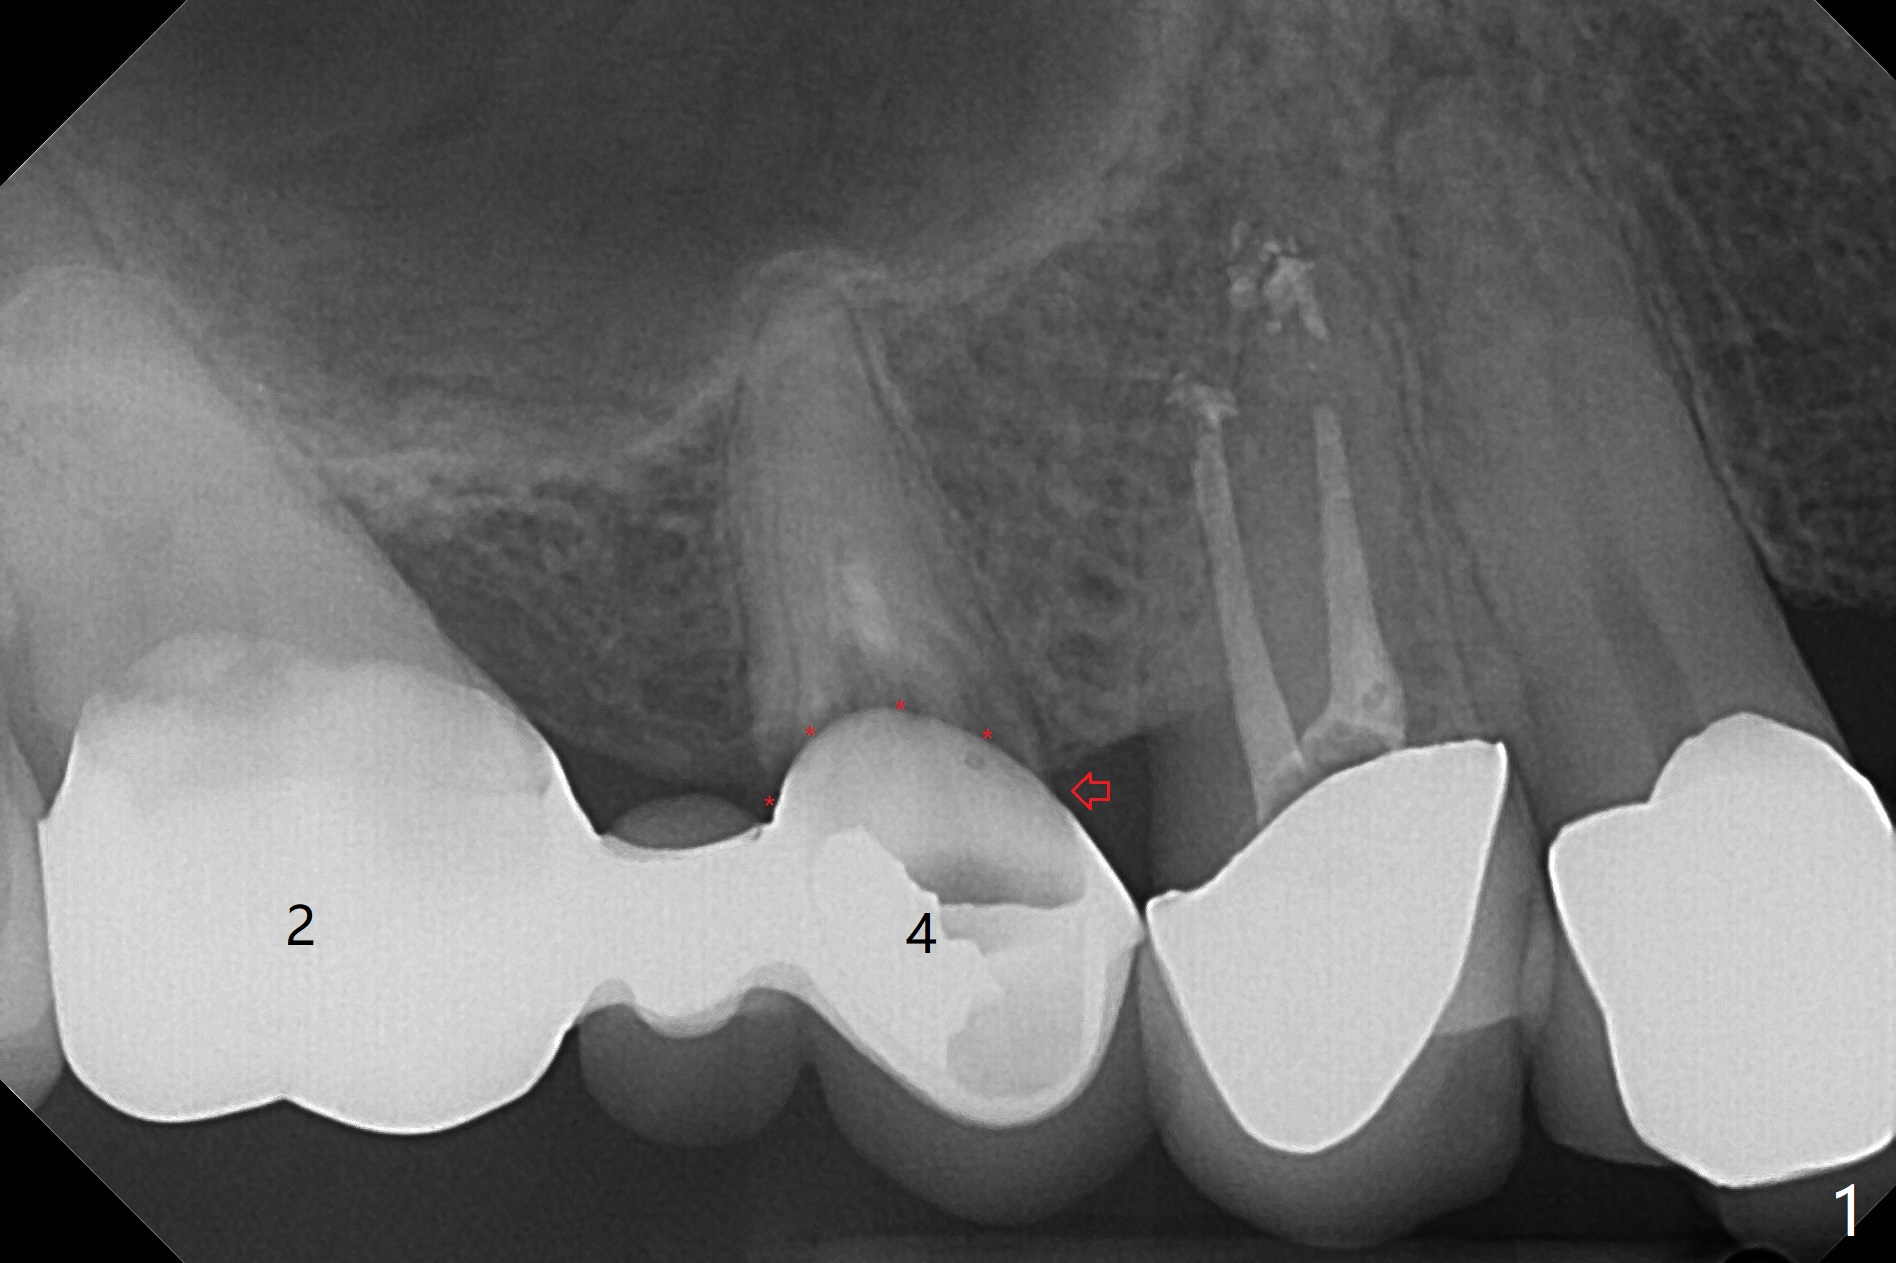

A 56-year-old man complains of food impaction under UR FPD (fixed partial denture, bridge). Floss goes through between #4 abutment and retainer (Fig.1 red arrow and *). After sectioning the FPD as indicated by black dashed line in Fig.2,3, try to initiate osteotomy at #3 with 1.2 and 1.5 mm drills for 5 mm (bone height) and 1.0 and 1.5 mm Tatum micro-osteotomes for sinus lift and place a 2x8.5 mm IS mini-implant. If it is feasible, place a 4x14 mm tissue-level implant slightly mesial at #4 (Fig.5). If not, place a larger one (5.0 mm) slightly distal for a cantilever FPD (Fig.4).